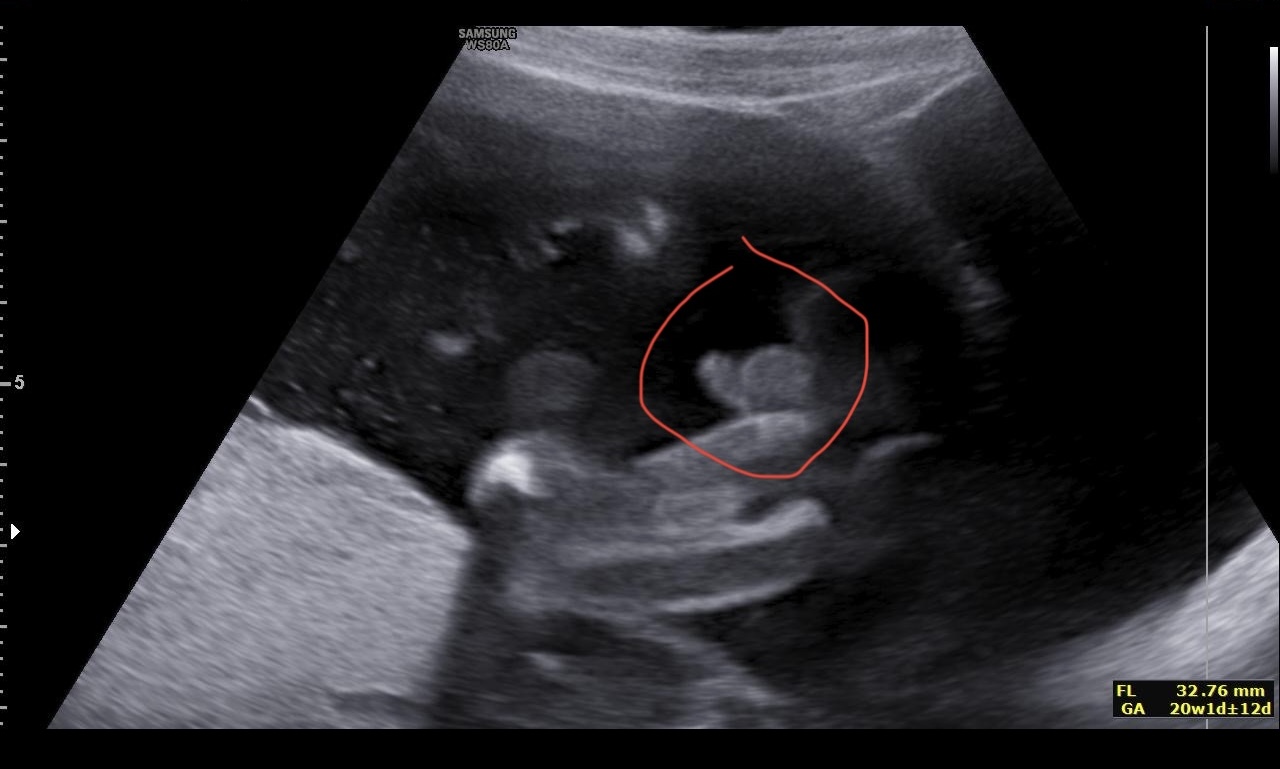

Tak jsme to, holky, moc netrefily, je to kluk😅😅😅

Já to trefila, na začátku diskuze jsem to psala😃😃Já tam prostě toho camprdlíka viděla 😃😃😃❤🌹Moc gratuluji 🌹🌹❤🤰

@terezie90 no ano, ty jediná jsi to říkala dobře😀🩷 já taky myslela, že je to celkem jasná holka😀🫣 Děkuju🙂

Já si myslím, že Klouček, ale to jsem si myslela i u svého miminka, a pak doktor mě vyvedl z omylu😃🙈🧡Přeji hodně štěstí v těhu 🍀🌹